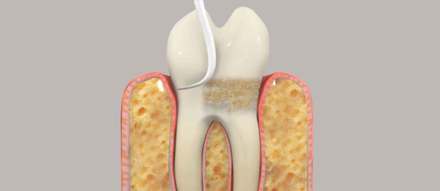

After scaling the tooth roots may need to be planed to smooth the root surface. Soft tissue will re-attach itself to a smooth tooth surface.